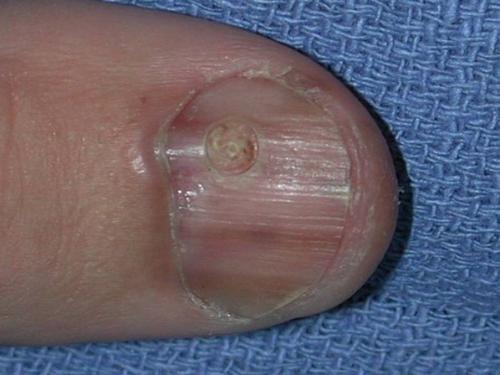

Как выглядит подногтевая меланома? Фото и признаки.

Все приведенные ниже картинки имеют гистологическое подтверждение, а не взяты из интернета. В квадратных скобках указан источник. Есть 2 наиболее частых признака:

Признак II

Наиболее частым признаком этого вида меланомы является симптом Хатчинсона – переход пигментации на ногтевой валик или кончик пальца. На 7 из 8 изображений, представленных ниже, виден этот признак. В то же время нельзя однозначно утверждать, что этот симптом бывает только при меланоме. Он может наблюдаться и при прозрачной кутикуле .

Подногтевая меланома большого пальца c 4-м уровнем инвазии по Кларку, толщина по Бреслоу не указана

Подногтевая меланома, толщина по Бреслоу 1,5 мм

Подногтевая меланома:

- Неоднородный цвет, нерегулярность полос при меланонихии.

- Треугольная форма полос.

- Распространяется на ногтевой пластине, свободном крае ногтя или кончике пальца.

- Разрушение или дистрофия ногтя.